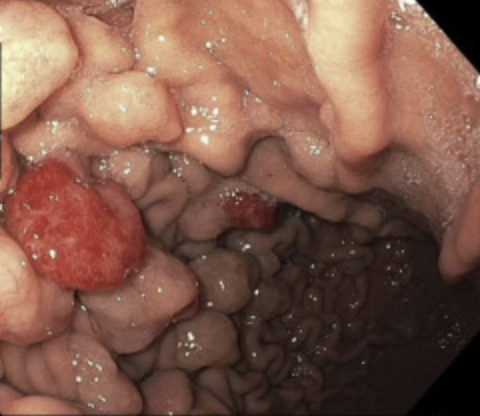

Enhanced Suction During Esophagogastroduodenoscopy: Official journal of the American College of Gastroenterology | ACG @AmCollegeGastro Congratulations @ZSobaniMD and @swathipaleti for putting this idea into video @AmJGastro #ThinkingOutsideTheBox #endoscopy #innovation